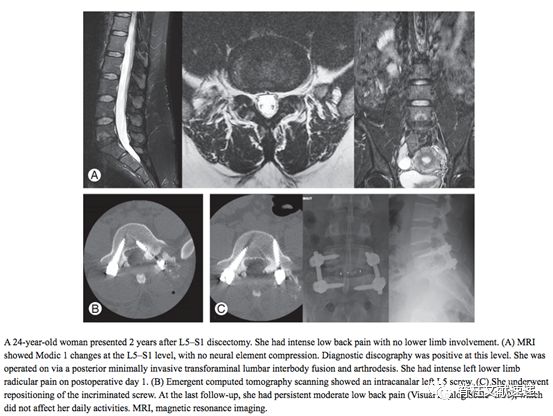

典型病例二:24岁女性患者,2年前行L5/S1髓核摘除术。患者存在明显的腰背痛,无下肢神经症状,椎间盘造影阳性。行固定融合术,术后1天严重左下肢根性症状,CT提示螺钉偏内,行翻修手术调整螺钉,末次随访患者VAS评分3分。